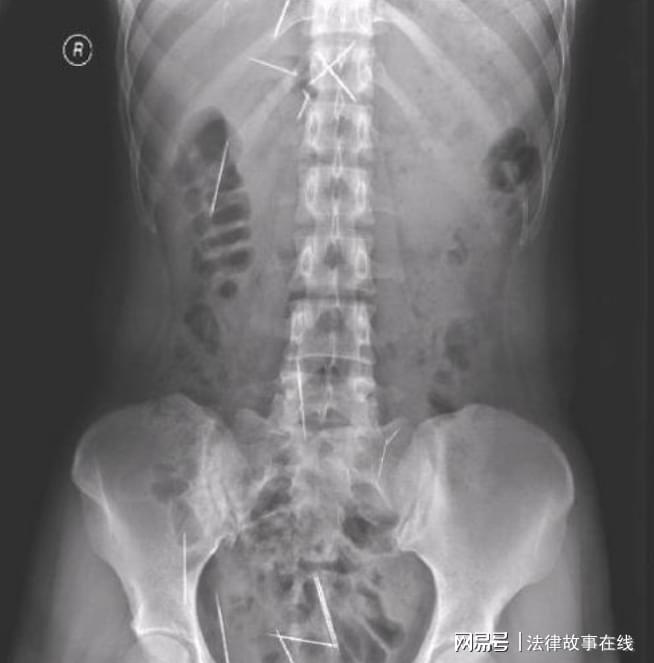

医生见他脸色煞白就接着说:“这个片子上显示,你太太的体内有二十六根缝衣针,分布在她的全身,头上有,脖子上有,胸腔、小腹还有胯骨上全都是,知道这是怎么回事吗?”

医生告知他们,这些针应该是一岁之前就插进去了,现在必须取出来,不然会危害生命。它们在体内不断游走,伤害性非常高,不过手术要分批进行,手术风险大,手术费大概也要三十万。

瑞奇德的手术专家告诉罗翠芬手术要分两次,不可能一次性成功,这过程会是漫长的,要有耐心和决心。罗翠芬点了点头,随后被推进了手术室。在经过12个小时的紧张作业后,罗翠芬体内的13根缝衣针被顺利取出。

针上布满铁锈,还连着体内的肌肉,剩余的十三根缝衣针,由四川原成都军区总医院承诺取出。在看过罗翠芬的病历档案,经开会研究,这次的手术定在半年以后,也就是2008年的2月份举行。

除了肺部的缝衣针,最危险的还有肝脏部位的针,足足有四根,且其中一根被折成了两段,这么危险的状况让十几年经验的医生都有些害怕。经过忙碌的十几个小时,罗翠芬体内的13根缝衣针全部被取出,手术结束后刘主任满身大汗。